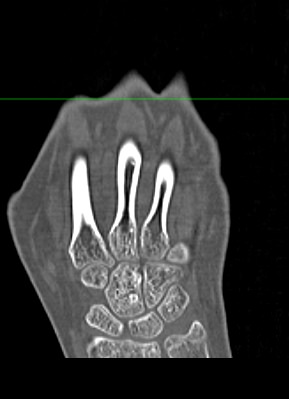

Кисти рук имеют сложное анатомическое строение. Кисть состоит из трех отделов:

- запястье (образовано 8-ю костями), которое участвует в формировании лучезапястного сустава;

- пясть (состоит из 5 трубчатых пястных костей);

- пальцы рук (состоят из 2 или 3 мелких трубчатых костей, соединенных межфаланговыми суставами).

Метод мультиспиральной КТ основан на использовании ионизирующего излучения, которое используется для послойного сканирования внутренних структур организма. Благодаря тончайшим срезам и последующей цифровой обработке полученных данных получаются послойные снимки и 3D-изображения кистей рук в мельчайших подробностях.

Наиболее распространенной причиной диагностической процедуры является травматическое повреждение. Переломы мелких костей на рентгенограмме зачастую могут визуализироваться неотчетливо за счет наложения костных структур друг на друга, а компьютерная томография позволяет различать все кости отдельно и является «золотым стандартом» для исключения повреждения костей.

Компьютерная томография лучше всего подходит для обследования костных структур, так как кости в большей степени поглощают рентгеновские лучи и поэтому хорошо видны на снимках. Для того, чтобы улучшить визуализацию мягких тканей, дополнительно проводится контрастное усиление. Обычно это применяется при подозрении на развитие опухолевых образований.